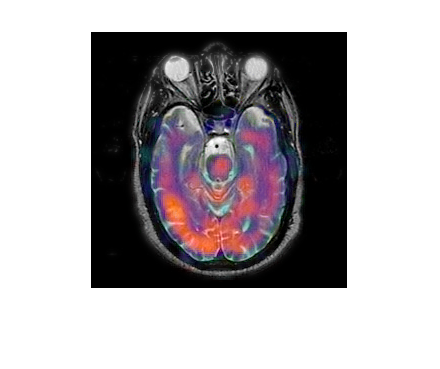

基于拉普拉斯重分解的多模态医学图像融合,核心是通过多尺度、精细化的拉普拉斯重分解拆分图像的低频结构与高频细节,再针对医学图像的临床需求(如结构完整性、病灶凸显性)设计分层融合规则,实现 CT/MRI、PET/CT 等多模态图像的信息互补,为临床诊断与手术规划提供更全面的视觉支撑。该方法突破传统拉普拉斯金字塔 “单一尺度分解” 的局限,通过重分解增强细节分离能力,兼顾融合精度与医学实用性。

多模态医学图像的融合目标是互补不同模态的优势信息:

PET 图像:反映代谢活性(如肿瘤恶性程度),但空间分辨率低、结构模糊。融合需实现 “结构 + 功能 + 细节” 的三维互补,确保医生能同时观察解剖结构与病理特征。

⛳️ 运行结果